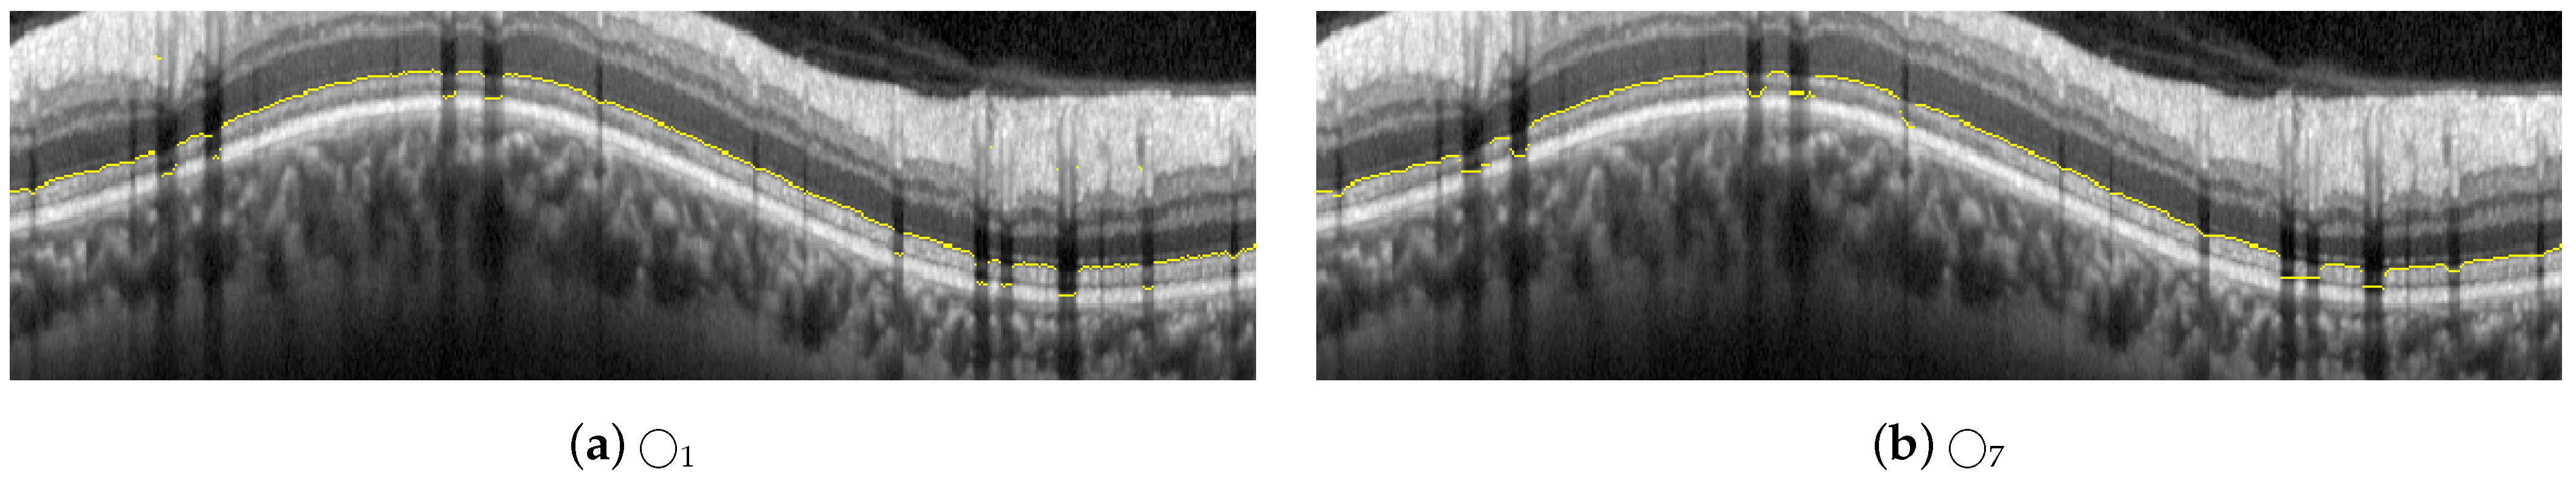

The proposed approach for the segmentation of the RNFL consists of a sequential process for obtaining different layer boundaries. Figure 4 illustrates the three boundaries used in the segmentation of the RNFL layer, namely #1-UB, #2-AB, and #3-LB.

The upper boundary of the RNFL, #1-UB, was outlined first, taking advantage of the high-contrast level between this layer and the upper area of the image. However, morphological preprocessing and the subsequent approximation with active contours are necessary in order to minimize the artifacts present in a large number of OCT images of the database. Section 2.5 describes this process in detail.

Obtaining the lower boundary of the RNFL, #3-LB involves a more challenging process, due to shadowing and artifacts caused by blood vessels as well as the low level of contrast between the RNFL and the lower layer, GCL. For this reason, the lower boundary of the ONL, #2-AB, was outlined and used as an auxiliary boundary which together with #1-UB, allowed us to obtain #3-LB in a third stage. Section 2.6 and Section 2.7 detail the estimation process of #2-AB and #3-LB, respectively, in which the morphological preprocessing and active contour smoothing were used again.